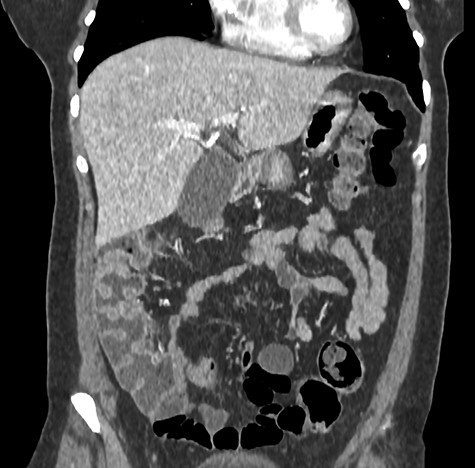

A 44-year-old female patient, without prior abdominal surgery, was admitted to the emergency department with an acute epigastric abdominal pain, without nausea. She presented similar episodes of pain in the past, without having ever requested a medical opinion. Physical examination revealed an acute epigastric pain without signs of peritonitis. Laboratory analyses were within normal limits. A computed tomography showed an internal hernia of the colon in the lesser sac, going back from the liver pedicle (Fig. 1). There were neither occlusion nor ischemia. We performed immediately a diagnostic laparoscopy with one 11-mm umbilical port and two 5-mm ports (one in the left lumbar and one in the hypogastrium). Exploration confirmed that the ascending colon and the right colonic flexure had herniated through the foramen of Winslow (Fig. 2). The colon was reduced with an atraumatic Johann’s graspers and was viable, cecum, ascending colon and the right colonic flexure was mobile due to a misapposition of the right Told fascia. To prevent recurrent herniation we performed the fixation to the lateral wall of the cecum, ascending colon and right colonic flexure with several non-absorbable sutures (Fig. 3). We did not perform the closure of the Winslow’s hiatus. Postoperatively, the patient recovery was uneventful and was discharged home 2 days later. A computed tomography was performed 1 month later for another reason, showing a good result of the right colon fixation on the lateral wall (Fig. 4). Twenty months after surgery, the patient totally recovered and has not experienced any recurrence or occlusion.

Postoperative computed tomography (coronal section) showed a good result of the right colon fixation on the lateral wall.